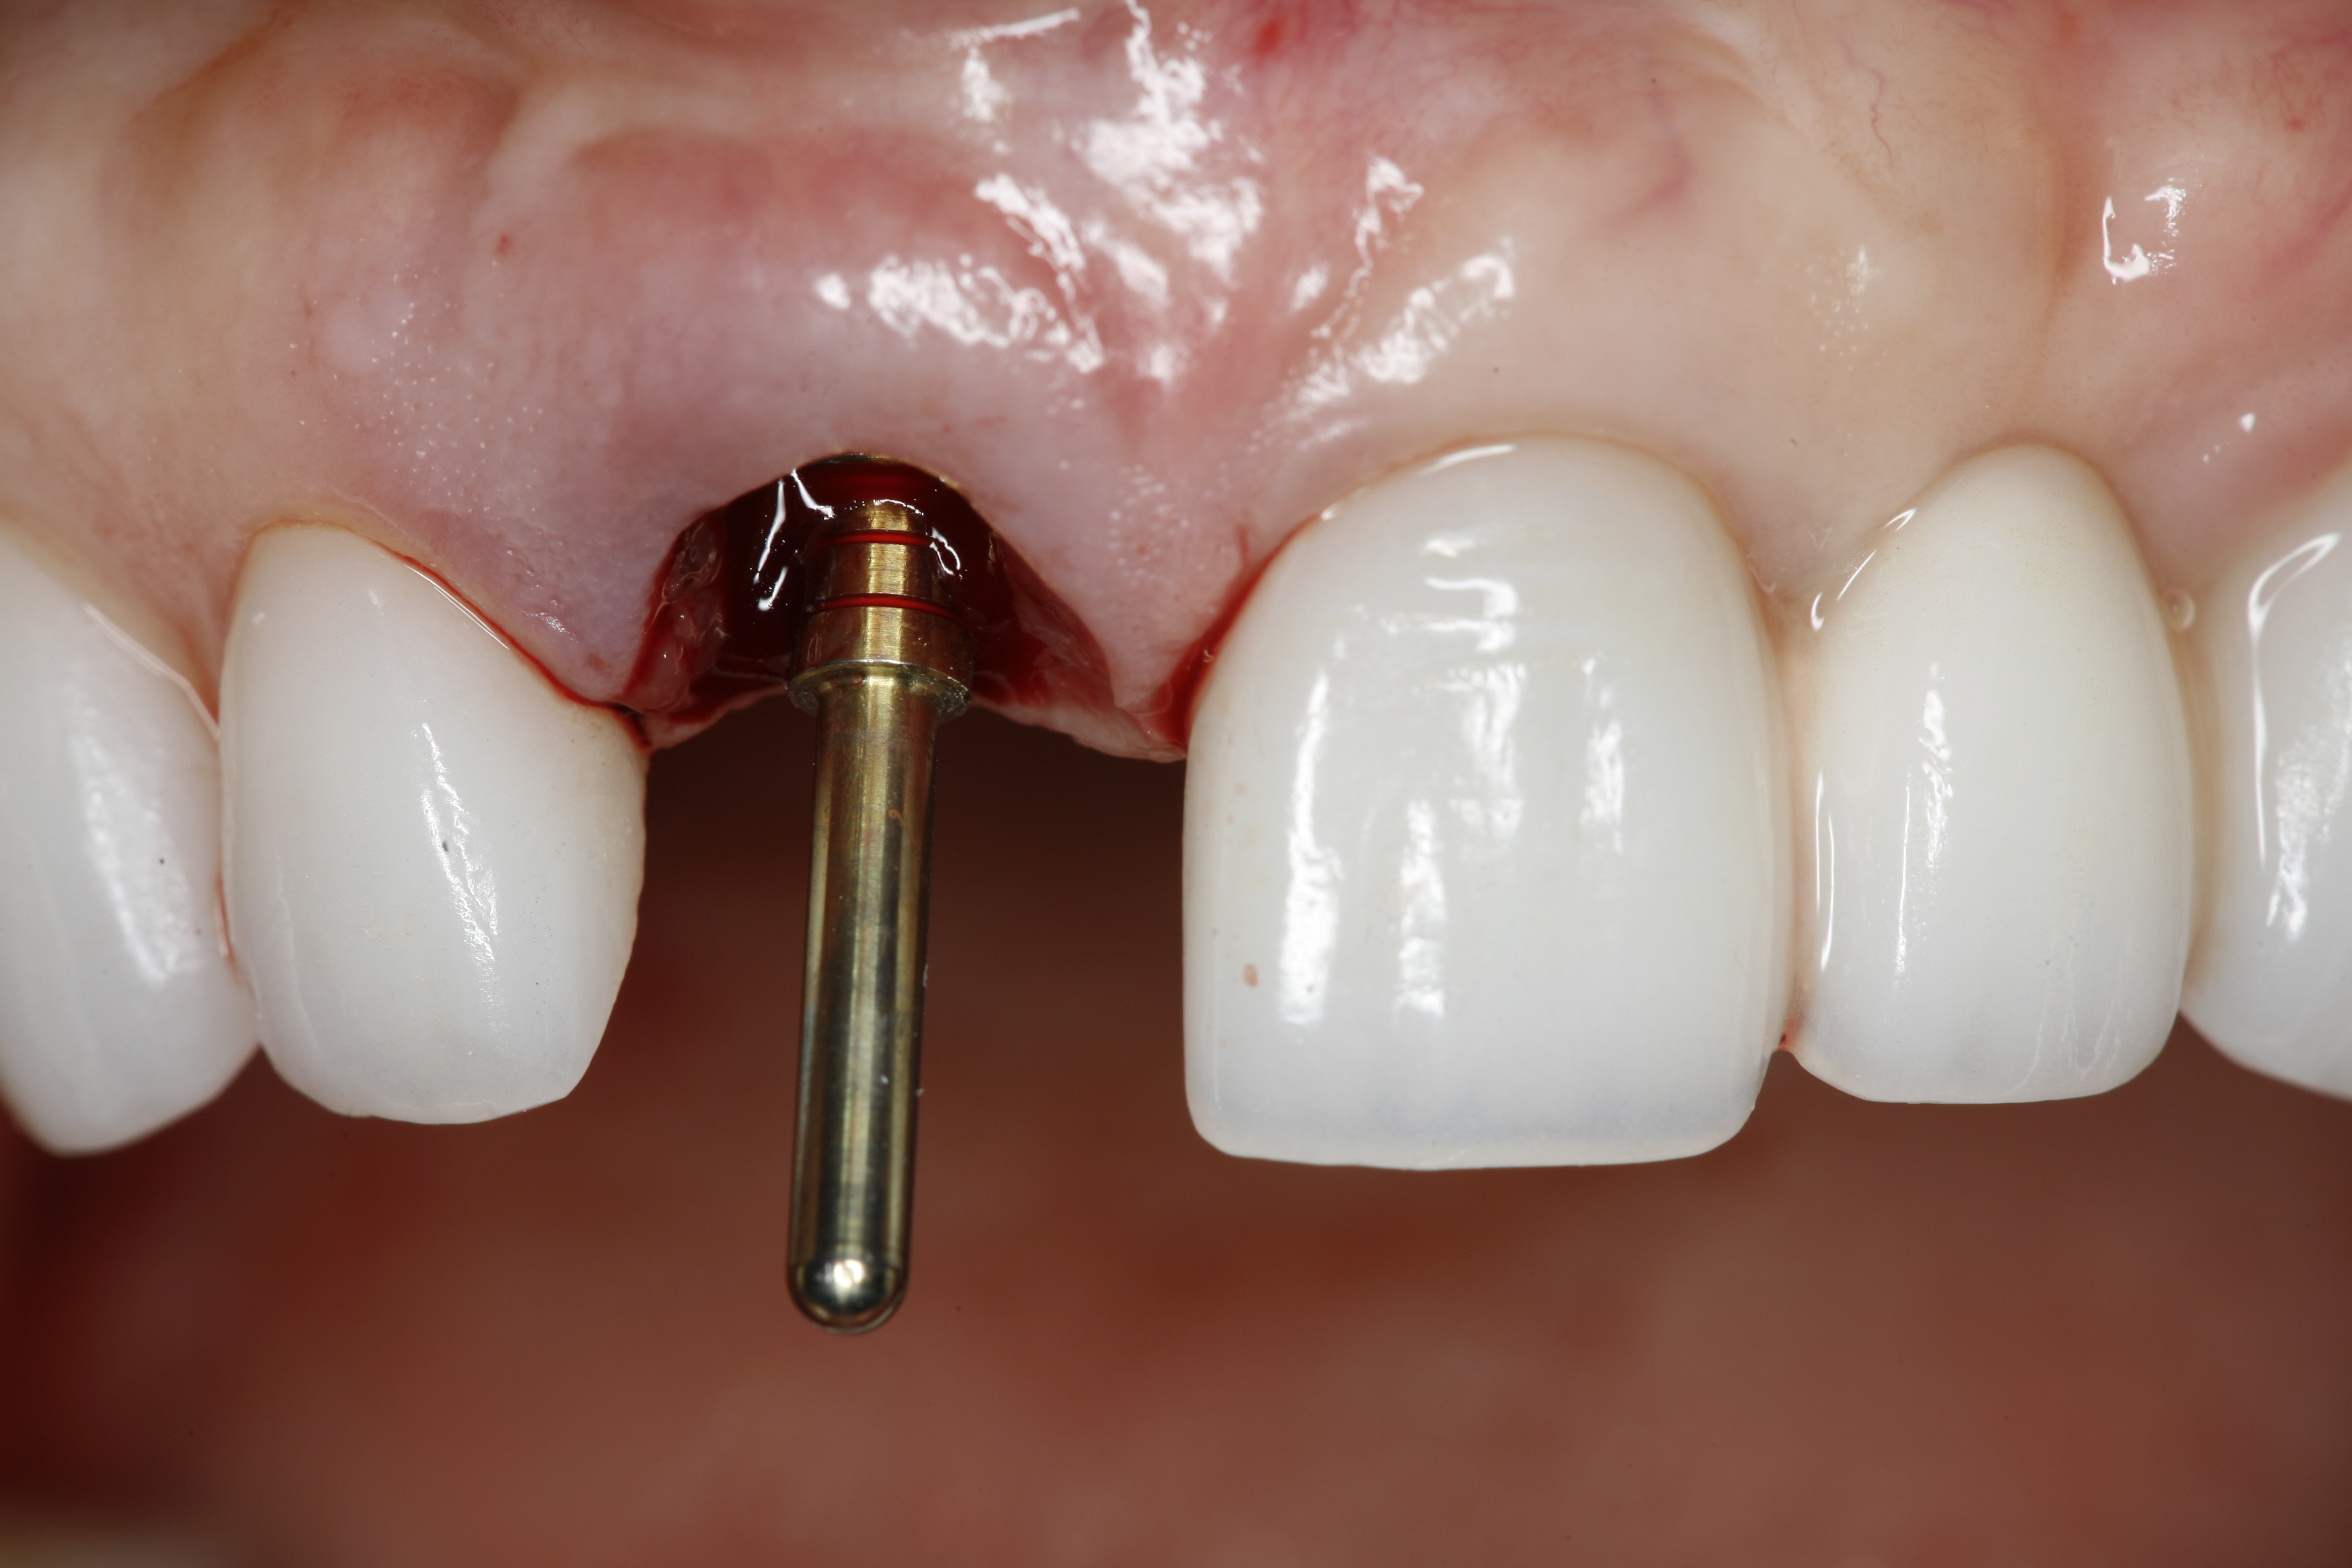

The implant impression, along with a cast of the opposing arch and shade, were sent to a commercial dental laboratory for fabrication of a master cast. A signed work order and the master cast were then sent to the BellaTek® Production Center (BIOMET 3i) for a lab-designed abutment (LDA) (Figure 14). A BellaTek® abutment was milled from a solid blank of titanium, and a gold-colored titanium-nitride coating was applied to impart a warm color through the thin marginal peri-implant tissues.

The master cast and abutment were returned to the laboratory for fabrication of the restoration (Figure 15). An all-ceramic crown (e.max®, Ivoclar Vivadent) was fabricated on the custom abutment; it matched the contours of the adjacent central incisor. After completion of custom shading, the definitive abutment and crown were returned to the restorative dentist. The abutment was tried in (Figure 16), and a radiograph was taken to confirm complete seating between the abutment/implant and the crown/abutment. The definitive abutment screw was torqued to 20 Ncm, and the screw-access opening was blocked out with Teflon tape.

Fig 16. Try-in of the definitive titanium-nitride–coated abutment.

Figure 16